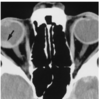

¿de qué enfermedad nos habla la siguiente imagen?

A

retinoblastoma bilateral y cuadrilateral